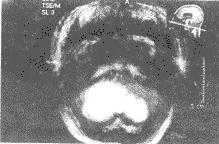

小腦梗塞臨床上一般將小腦梗塞分為三種類型:良性型、假腫瘤型和昏迷型,無論哪一型小腦梗塞發病時都會有頭暈、步態不穩、噁心嘔吐等臨床表型,但後兩種除了小腦症候群外還可以合併偏癱甚至出現昏迷,臨床治療一般給予降纖、抗凝、抗血小板聚集、活血化瘀芳香開竅中藥及脫水降顱壓等藥物治療。